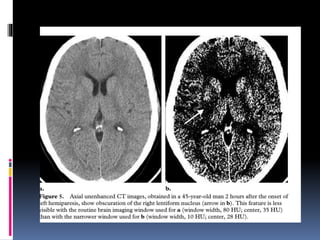

CTA shows an abrupt “cutoff” with a meniscus of contrast in the

proximal left MCA. Contrast in the distal M2 and M3 segments is

caused by slow retrograde collateral flow from pial branches of

the ACA across the watershed to M4 (cortical) branches .

CTA shows anabrupt “cutoff” with a meniscus of contrast in the proximal left MCA. Contrast in the distal M2 and M3 segments is caused by slow retrograde collateral flow from pial branches of the ACA across the watershed to M4 (cortical) branches .